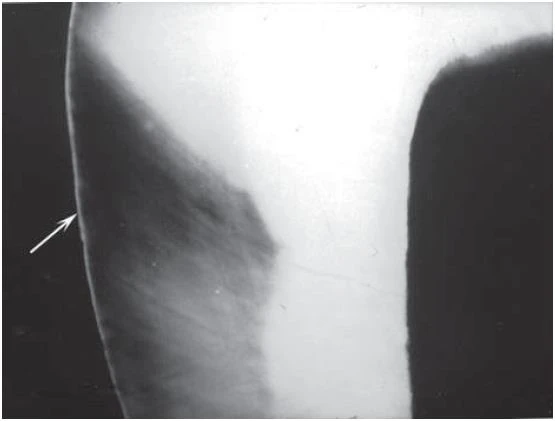

X quang rất hữu ích trong việc phát hiện sâu răng vì quá trình tiến triển sâu răng gây mất khoáng men và ngà răng. Tổn thương có hình ảnh thấu quang trên phim X quang (tối hơn) vì vùng mất khoáng răng không hấp thụ nhiều photon của tia X. Mặc dù vậy, có một điều quan trọng cần ghi nhớ đó là tổn thương được phát hiện trên X quang cho thấy hoạt động vi khuẩn trên bề mặt răng chứ không cho biết liệu tổn thương này đang hoạt động hay đang ngừng tiến triển. Một tổn thương cũ không còn hoạt động nữa cũng sẽ có hình ảnh “vết sẹo” mất khoáng trên nền mô cứng. Lý do việc tái khoáng hoá chỉ xảy ra ở phần bề mặt bên ngoài nhất là vì dung dịch chứa chất khoáng từ nước bọt không thể khuếch tán vào phần thân của thương tổn. Do X quang chỉ phản ánh mức độ mất khoáng ở hiện tại nên chỉ mình phim X quang không thể phân biệt được giữa tổn thương đang hoạt động và một tổn thương ngừng tiến triển. Một phim X quang thứ hai chụp vào thời gian sau đó có thể cho biết liệu tổn thương có đang hoạt động hay không. Khi đưa ra quyết định theo dõi một tổn thương thì nên cân nhắc những nhân tố như vệ sinh răng miệng, liệu pháp fluor, tình trạng tiết nước bọt, chế độ ăn uống, tiền sử sâu răng, mức độ chăm sóc miếng trám và độ tuổi để xem xét thời gian giữa các lần chụp X quang.

Hình 2. Hình ảnh X quang của tổn thương sâu răng không hoạt động (vùng đen), một nửa xuyên qua men răng vẫn còn nguyên vẹn, với bề mặt được khoáng hoá (mũi tên)